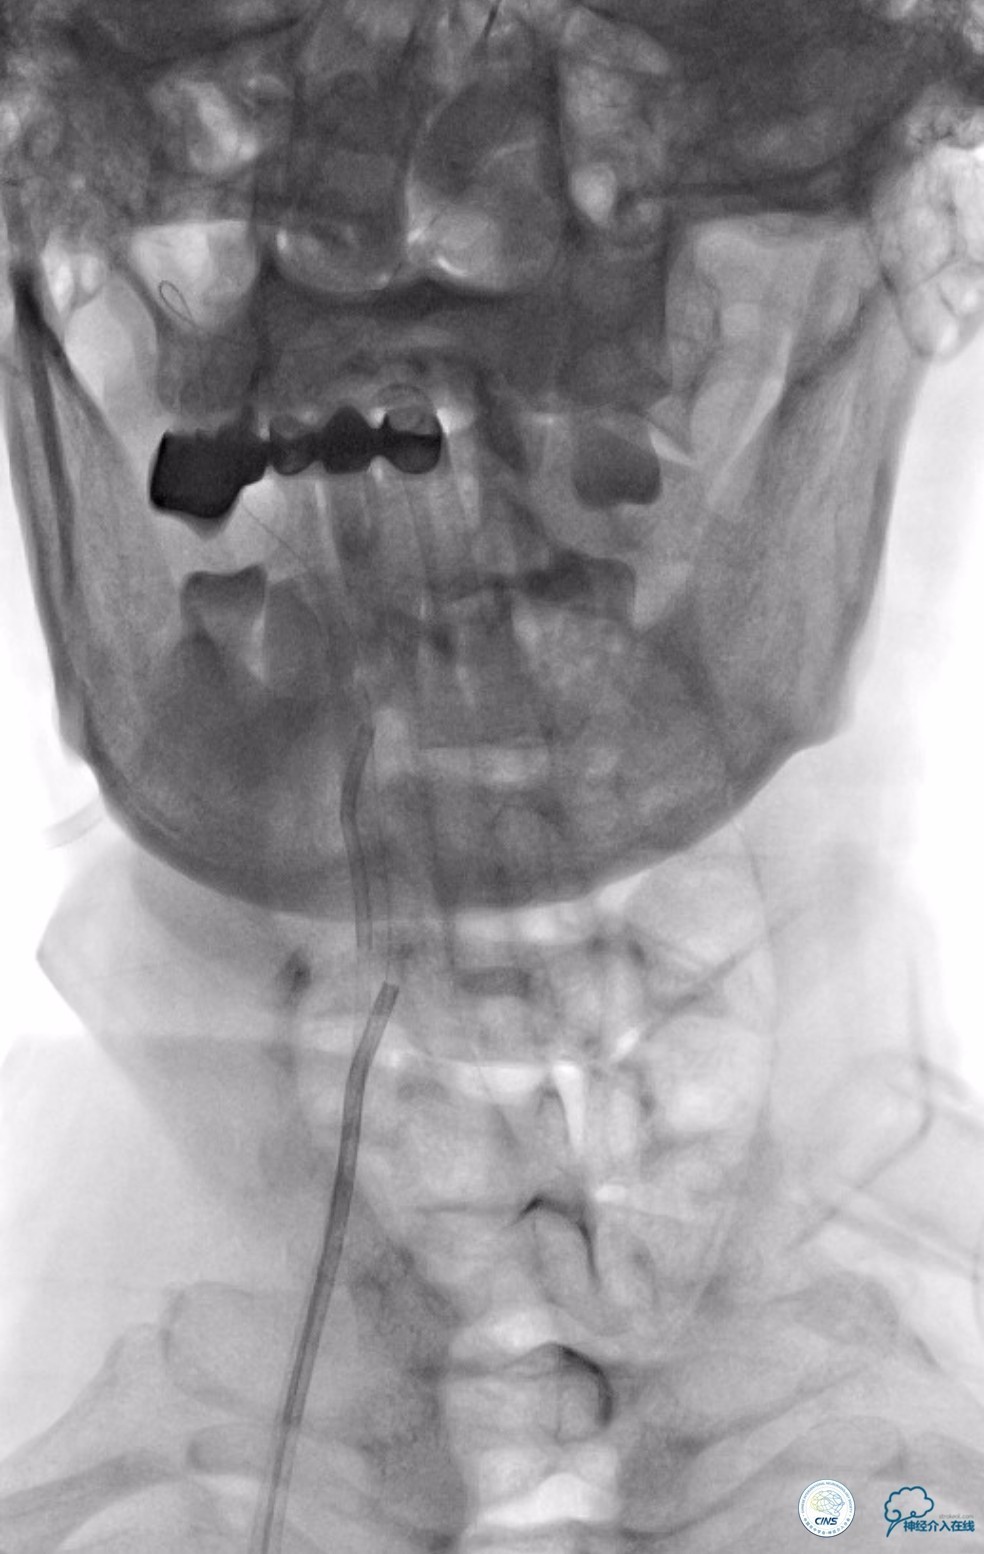

动脉粥样硬化狭窄合并动脉瘤的处理,因治疗狭窄和栓塞动脉瘤的两套系统常需要并列使用,事先要考虑所用导引导管是否能完全容纳两套系统,如本例8F导引导管到位困难,故只能改用两套系统完成治疗(图14)。

图14

此外对于邻近动脉瘤的狭窄扩张时,可以考虑使用长度稍长一点的球囊,尽量覆盖动脉瘤颈,避免扩张过程中球囊损伤动脉瘤。